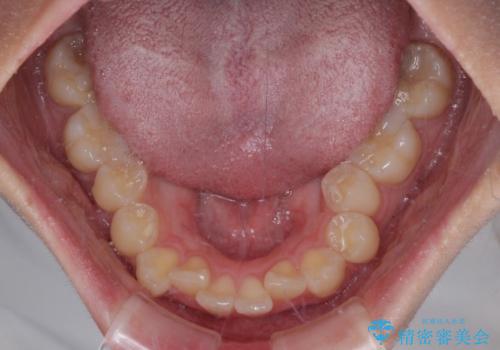

1年弱の短期間で、望み通りのスッキリとした口元に仕上げることができました。

- 11ヶ月